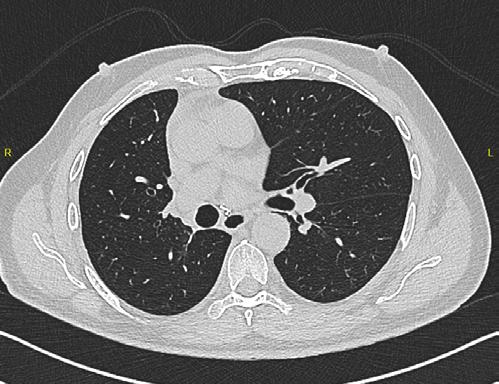

La TC de baja dosis, es la modalidad de imagen más utilizada como método de escrutinio para la detección de lesiones pulmonares, es un estudio rápido, que no requiere preparación previa. ESCANERS DE UN PACIENTE CON

Figura 1-4. Estudio de tomografía simple de tórax, con reconstrucción volumétrica, multiplanares con ventana para pulmón y en mediastino (, en donde se observa el nódulo pulmonar sólido de bordes lobulados hipodensos.

Se presente al caso de un masculino de 80 años de edad que acude por presentar tos en estudio de 3 meses de evolución, sin datos de fatiga, como antecedente de importancia tabaquismo por lapso de 40 años a razón de 1 cajetilla y media diaria (exposición de 60 paquetes año), actualmente suspendido.

Se le realiza estudio de tomografía simple de tórax en donde se encontró en el segmento anterior del lóbulo inferior derecho nódulo sólido, con diámetro de 22mm, volumen de 2.9ml, condiciona disminución del bronquio segmentario, con secreciones endoluminales distales, de acuerdo a la clasificación de LUNG RADS con categoría 4B, alta sospecha de malignidad. Sin evidencia de lesiones nodulares en el resto del parénquima.

Los programas de tamizaje para cáncer de pulmón con TC de tórax de baja dosis, han demostrado disminuir la mortalidad, con una reducción de hasta 26% en algunas series.

El sistema LUNG RADS para la evaluación de nódulos pulmonares observados en TC de tórax de baja dosis, establece categorías del 0 al 4, dividiendo ésta última en 4A, 4B y 4X, en el caso de los nódulos 4B se establece que son nódulos sólidos con diámetro de 15 mm en el estudio basal o nódulos subsólidos con porción sólida de 8 mm, en la versión actualizada del 2022, se agregan quistes aéreos atípicos con engrosamiento mural o componente nodular mural. La recomendación para esta categoría es la realización de PET CT y/o toma de biopsia.

La estandarización del reporte y las recomendaciones para el seguimiento dadas por el sistema LungRADS permiten una sistematización del abordaje, estableciendo parámetros de sospecha de cáncer de pulmonar que permitan realizar el diagnóstico temprano, así como disminuir los falsos positivos y sobrediagnóstico del cáncer pulmonar.